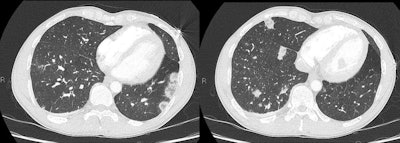

"Aspiration pneumonitis and pulmonary edema are also common in the abuse of several drugs," they noted. "Aspiration frequently occurs in the setting of overdose, especially with CNS depressants. Pulmonary edema can occur with cocaine, opiates, and methamphetamine abuse."

"Crack lung" is an acute pulmonary syndrome that occurs within 48 hours of smoking crack cocaine. Patients present with dyspnoea, chest pain, hemoptysis, and/or fever. CT shows diffuse alveolar and interstitial opacites, often ground glass in nature, and occasionally with small pleural effusions. The appearance is clear with cessation of the drug. Pneumomediastinum is also seen with crack cocaine smoking, the authors noted.